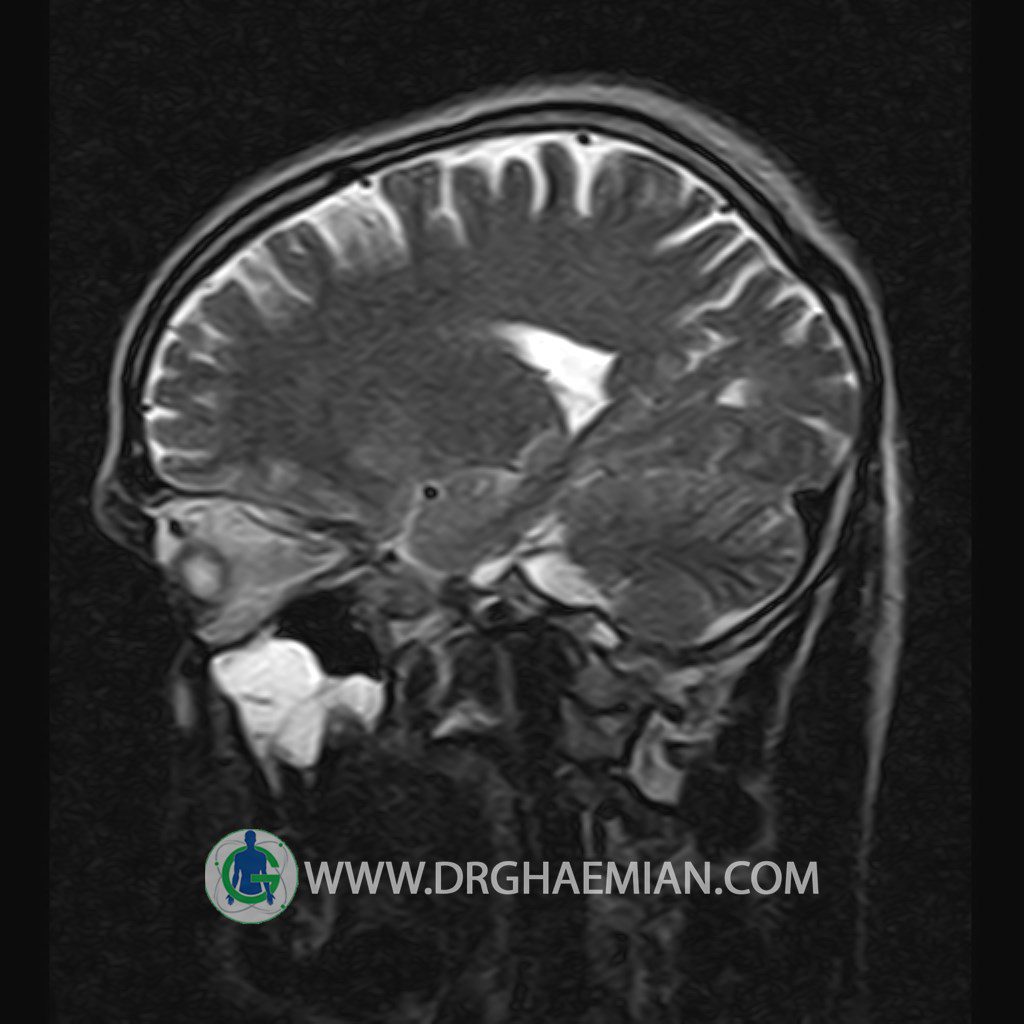

پزشکان اغلب از تصویربرداری ام آر آی برای تشخیص و درمان عارضه های پزشکی که فقط با استفاده از اشعه ایکس یا میدان مغناطیسی و امواج رادیویی قابل مشاهده است، استفاده می کنند. دستگاه ام آر آی تصاویر دقیق از ساختار های داخلی بدن ایجاد می کند. در این کیس یک میکروآدنوم در هیپوفیز بیمار مشاهده می شود.

HYPOPHYSIS MRI

(with and without contrast)

Technique: Axial , coronal T1 , Axial , coronal , sagittal T2 , Axial, coronal T1 post Gd & 64 dynamic thin coronal slices.

REPORT :

The infundibulum is centered and of normal size .

The optic chiasm and suprasellar spaces appear normal .

The cavernous sinus and imaged portions of the internal carotid artery and carotid siphon are unremarkable .

Evaluable portions of the neurocranium show no abnormalities .

The sphenoid sinus is clear and pneumatized .

Imaging of the hypothalamus after contrast medium administration was normal.

– Small hypoenhancing mass lesion ( 3 x 4 mm ) in posterior of pituitary stalk suggestive for micro adenoma

– Mucosal thickening in ethmoid & maxillary sinuses

is seen